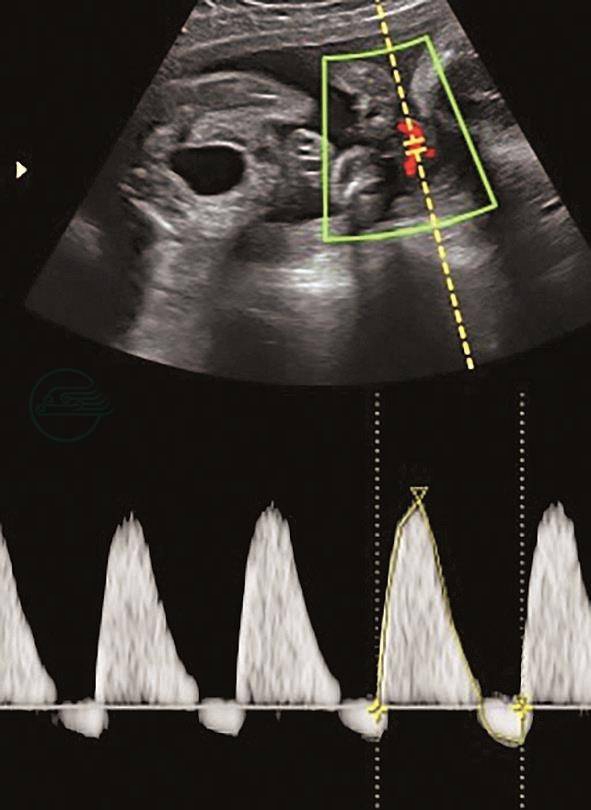

图2脐动脉

妊娠27+2周,脐动脉舒张期血流反向